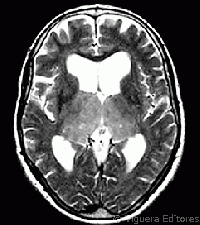

2. Amnesia en las demencias

1. Desorientación espaciotemporal

1. Desintegración general de los proceso cognoscitivos

2. Amnesia en tumores cerebrales

1. los tumores profundos invaden o comprimen estructuras limbicas

1. origina trastornos amnésicos